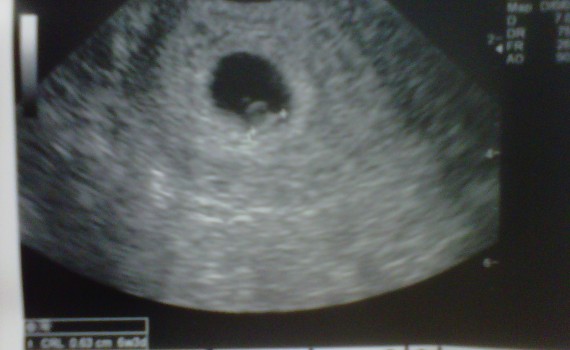

We had our first ultrasound on Wednesday (8/8/11) and saw the heartbeat!! YAY!  Our baby was measuring perfectly at 6 weeks and 3 days.   Will came to my work, and our nurse, Gayle, did the scan for us.  In 3 more weeks we go to my OB where we will […]

Heartbeat!